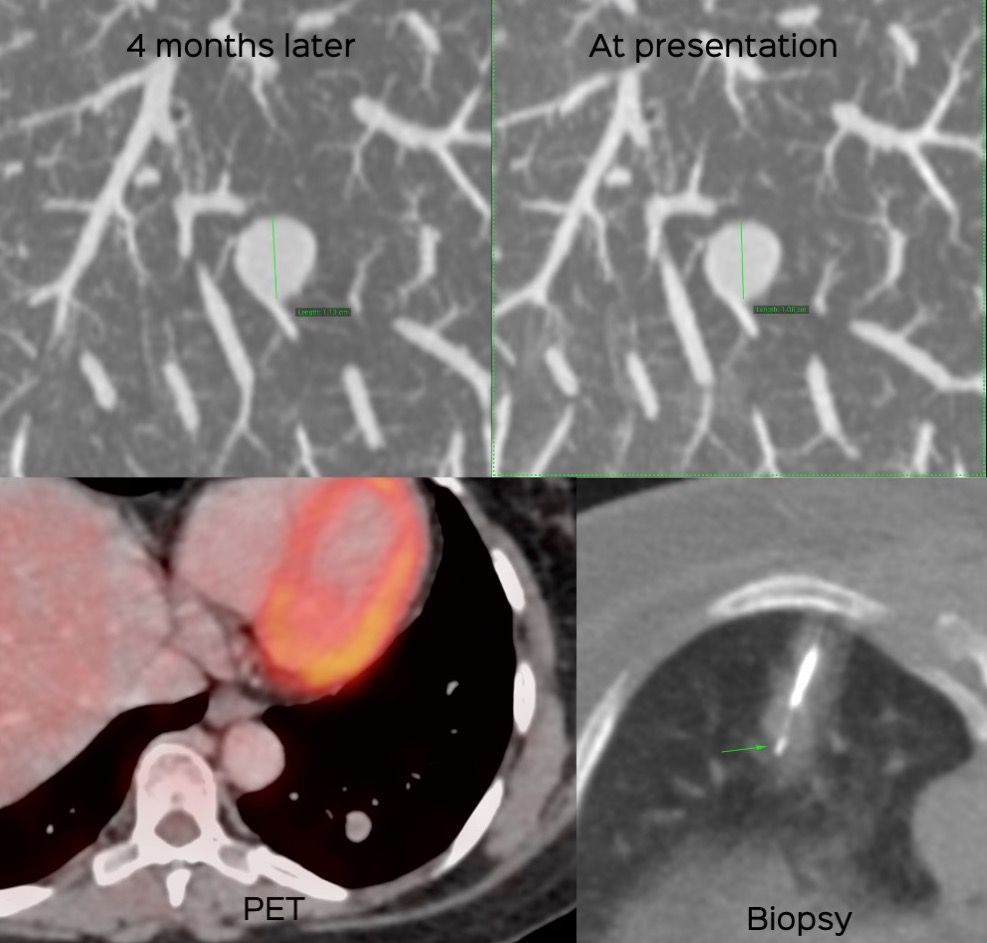

Case 31: The Curious Case of an Incidentally Detected Lung Nodule in a Middle-Aged Woman Members Public

54-years old woman with an incidentally detected growing lung nodule and an unusual diagnosis